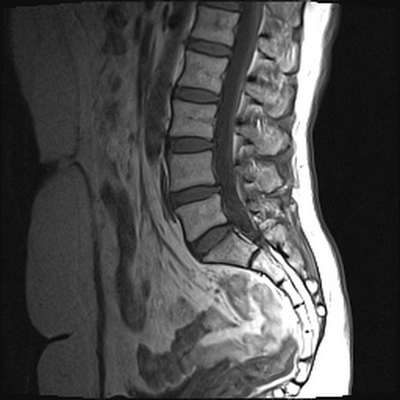

Магнитно-резонансное сканирование пояснично-крестцового отдела позвоночника: множественные гемангиомы (сагиттальная плоскость, Т1 ВИ)

Расшифровка результатов МРТ включает оценку:

- очагов с патологическим МР-сигналом (на участках субхондрального склерозирования, при пролапсах дисков, сужении межпозвонковых отверстий, поражении нервных корешков, в области отека, воспаления и др.);

- плотности задней продольной связки;

- конфигурации тел визуализируемых позвонков:- высота, структура, поверхность (отсутствие остеофитов - костных разрастаний, грыж Шморля), состояние опорных площадок и пр.;

- дурального мешка (защитной оболочки спинного мозга);

- оси позвоночника на исследуемом уровне;

- размеров спинномозгового канала;

- щелей дугоотросчатых суставов;

- структуры, контуров, диаметра спинного мозга;

- состояния паравертебральных мягких тканей, связочного аппарата;

- кровоснабжения спинного мозга и пр.